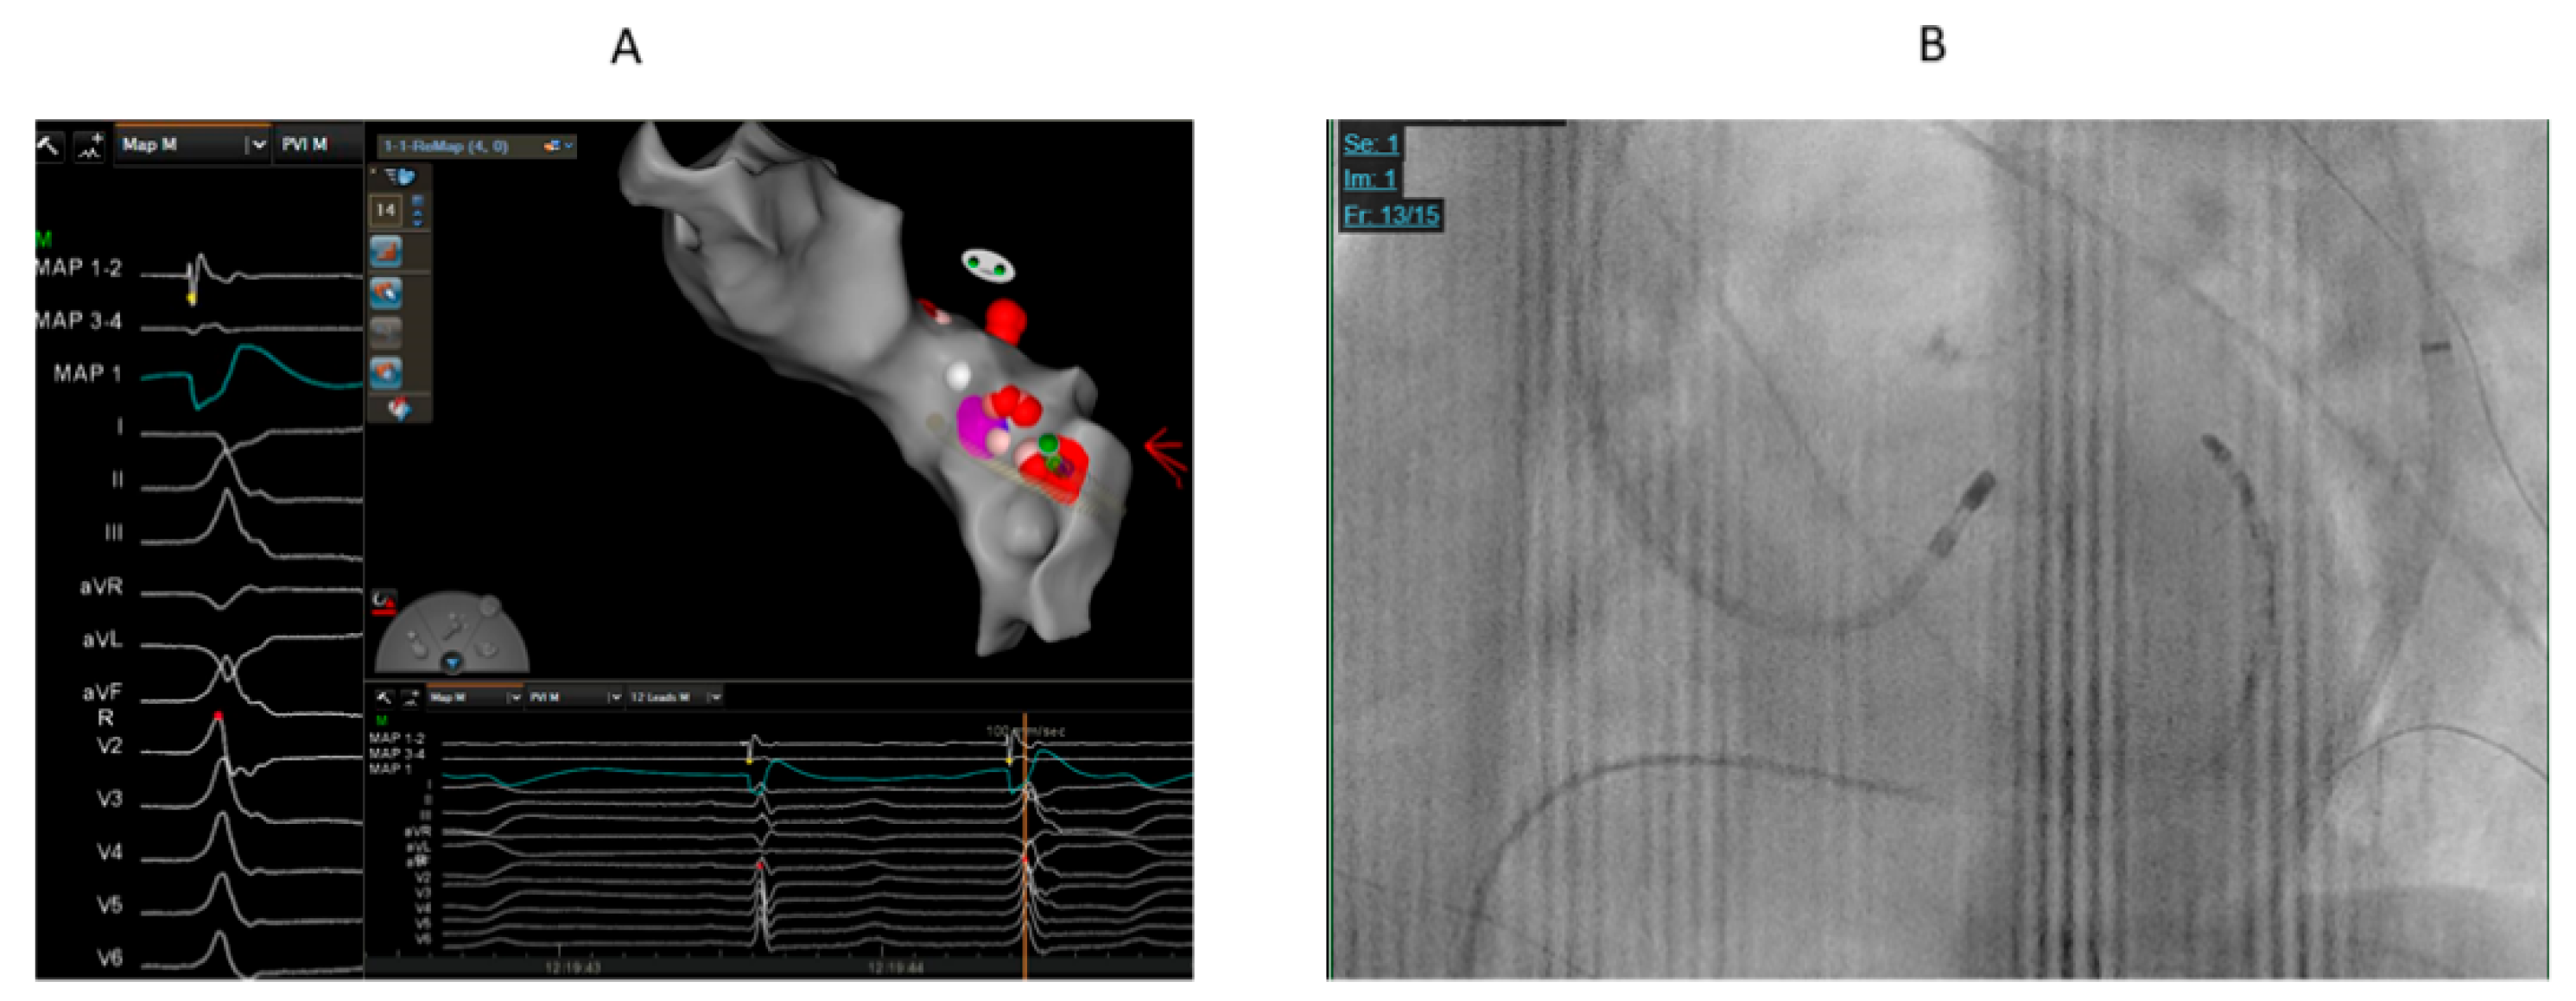

Table 2 summarizes the sites of ablation. Seventeen patients had successful ablation from LVOT below LCC or the right-left coronary junction (Figure 1 and Figure 2). Sequential ablation at LCC and LVOT was successful in 8 out of 9 patients. Sequential ablation from LVOT/LCC and RVOT/LPC was succesful in 7 patients.

Figure 1. 68 years old male with high burden VPCs (RBBB pattern and inferior axis) and mildly reduced left ventricular function. A. The earliest activation (19 ms before QRS) was at LVOT below and lateral to left coronary cusp. We could not advance catheter to GCV-AIV. We supposed that the origin might be close to GCV-AIV. Cluster ablation for prolonged duration (240 ms) at lateral part of LVOT summit was performed that eventually eliminated the VPCs. B. The catheter ablation at successful ablation site at LVOT.

Figure 2. 33 years old male with high burden VPCs with V3 transition and inferior axis. A. The earliest activation was at GCV-AIV junction. However, ablation was judged to be unsafe in this site because of proximity to coronary arteries. Ablation at LVOT adjacent to earliest site failed to eliminate VPCs in first ablation. B. In redo procedure, prolonged duration (240 ms) anatomical ablation at LVOT adjacent to earliest site at GCV-AIV as showed by electroanatomical mapping successfully eliminated the VPCs. C. Fluoroscopic image showing the ablation catheter in LVOT adjacent to diagnostic catheter at GCV-AIV.